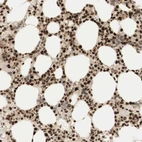

Immunohistochemical staining of human bone marrow shows strong nuclear positivity in hematopoietic cells.